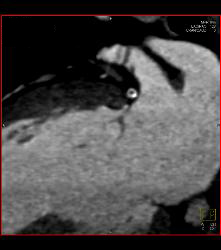

Left Anterior Descending Coronary Artery (LAD) and Right Coronary Artery (RCA) Disease